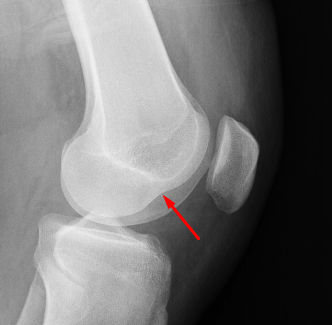

Age: 17

Sex: Male

Indication: Knee injury

Sample ReportAcute avulsion fracture along the lateral tibial plateau (Segond fracture) and impaction fracture of the lateral femoral condyle, both of which are associated with ACL tears. Recommend knee MRI for further evaluation.

Mild lateral patellar tilt.

Moderate-sized joint effusion.